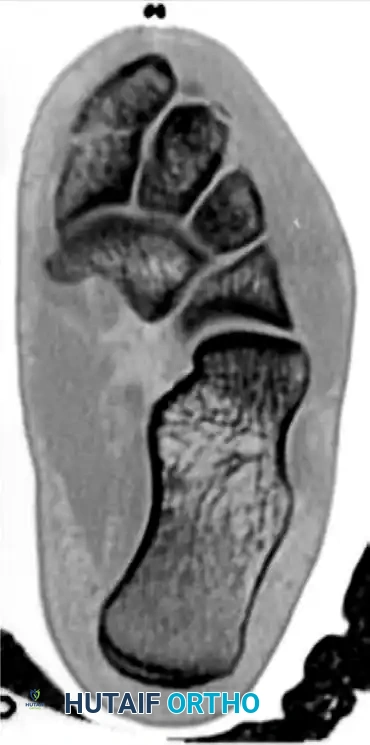

FIGURE 2: Preoperative axial CT scan confirming the comminution and displacement of the medial cuneiform fracture (asterisk), providing critical detail for preoperative planning.